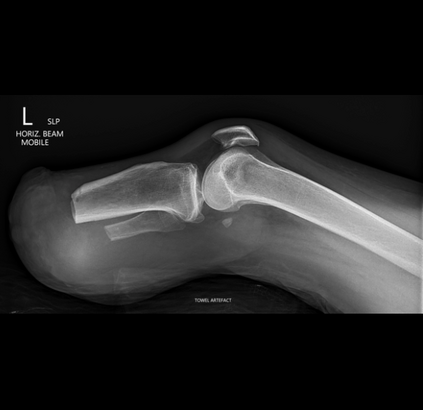

In this study, we aim to initiate the development of Radiology Foundation Model, termed as RadFM.We consider the construction of foundational models from the perspectives of data, model design, and evaluation thoroughly. Our contribution can be concluded as follows: (i), we construct a large-scale Medical Multi-modal Dataset, MedMD, consisting of 16M 2D and 3D medical scans. To the best of our knowledge, this is the first multi-modal dataset containing 3D medical scans. (ii), We propose an architecture that enables visually conditioned generative pre-training, allowing for the integration of text input interleaved with 2D or 3D medical scans to generate response for diverse radiologic tasks. The model was initially pre-trained on MedMD and subsequently domain-specific fine-tuned on RadMD, a radiologic cleaned version of MedMD, containing 3M radiologic visual-language pairs. (iii), we propose a new evaluation benchmark that comprises five tasks, aiming to comprehensively assess the capability of foundation models in handling practical clinical problems. Our experimental results confirm that RadFM significantly outperforms existing multi-modal foundation models. The codes, data, and model checkpoint will all be made publicly available to promote further research and development in the field.